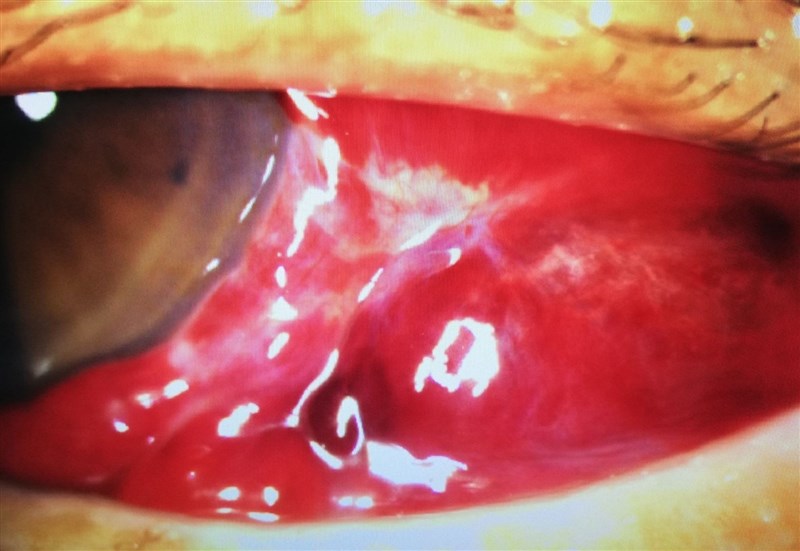

天氣忽冷忽熱,眼科門診出現「紅眼族」,醫生說是熱脹冷縮造成微血管破裂而形成「結膜下出血」。圖/達特楊眼科聯盟提供

【記者王淑芬高雄報導】天氣忽冷忽熱,眼科門診出現「紅眼族」。眼科醫生說,多因天氣熱脹冷縮造成微血管破裂,致患者眼白變紅導致「結膜下出血」;雖然紅眼對視力沒有影響,也不會交互傳染,但提醒民眾勿用力搓揉,避免眼球血腫,甚至壓迫視神經而失明。

年約20歲的陳女在寒冷的冬天起床後發現左眼好像被大血塊包住,剛開始因眼睛不會刺痛,而且視力沒有受影響而未加理會。達特楊眼科聯盟執行長洪啟庭今天指出,這種「紅眼睛」多因天氣熱脹冷縮致微血管破裂,血液流到結膜下方所導致,提醒千萬勿揉眼睛,以避免眼球血腫、壓迫視神經而失明。

他說,陳女雙眼近視600度,左眼(紅眼睛)最佳矯正視力仍有0.8,結膜下出血屬於嚴重程度,她的雙眼壓正常等,考量個案沒有外傷史造成眼睛紅,也無服用高血壓或通血路藥物,於是醫生給予類固醇藥水以降低血液滲漏及減少出血,還有眼用抗生素以避免眼睛的二次感染等。醫囑勿揉眼睛,病程大約2至3周可以恢復。

詎料,陳女於就醫5天後匆忙回診,而且原先的結膜下出血變得更嚴重,外觀已成了一顆深紅色的眼睛。

原來陳女因擔心紅眼睛問題,每天熱敷約30次,甚至還用力搓揉眼睛,希望揉散出血處。直到第5天,左眼明顯嚴重血腫及眼球無法轉動,視力出現複視,走路也失去平衡等。

圖/達特楊眼科聯盟提供

洪啟庭說,陳女就醫做視力檢查,視力大幅減退、眼壓飆升,經頭部與眼眶電腦斷層,竟發現她的軸向視圖出現大片血塊於左眼球後方,致眼球肌肉運動受限,是造成陳女左眼無法正常轉動形成複視的原因。所幸,陳女眼球後血腫位置偏下方,沒有明顯壓迫到視神經,否則就失明之虞。